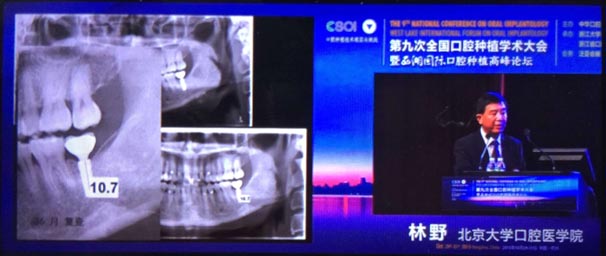

20151029日第九次全國(guó)口腔種植學(xué)術(shù)大會(huì)暨西湖國(guó)際口腔種植高峰論壇在浙江省人民大會(huì)堂隆重開幕。這是中華口腔種植專業(yè)委員會(huì)主辦的兩年一度的全國(guó)性學(xué)術(shù)會(huì)議,代表了中國(guó)口腔種植學(xué)發(fā)展的水平和方向。

會(huì)議期間國(guó)內(nèi)知名口腔專家針對(duì)當(dāng)前口腔種植領(lǐng)域熱點(diǎn)進(jìn)行了精彩的學(xué)術(shù)演講。其中北京大學(xué)口腔醫(yī)學(xué)院林野教授的演講主題是種植體設(shè)計(jì)及臨床意義。

威高演講中林野教授對(duì)國(guó)產(chǎn)品牌WEGO牙種植體系統(tǒng)的設(shè)計(jì)和臨床表現(xiàn)表示肯定,向在座觀眾展示了WEGO牙種植體系統(tǒng)的臨床病例。病例對(duì)76WEGO牙種植體進(jìn)行了平均21個(gè)月的追蹤觀察,結(jié)果表明WEGO牙種植體脫落、松動(dòng)、種植體周圍病現(xiàn)象均為0,頸部骨吸收平均值為0.20mmSD0.07。